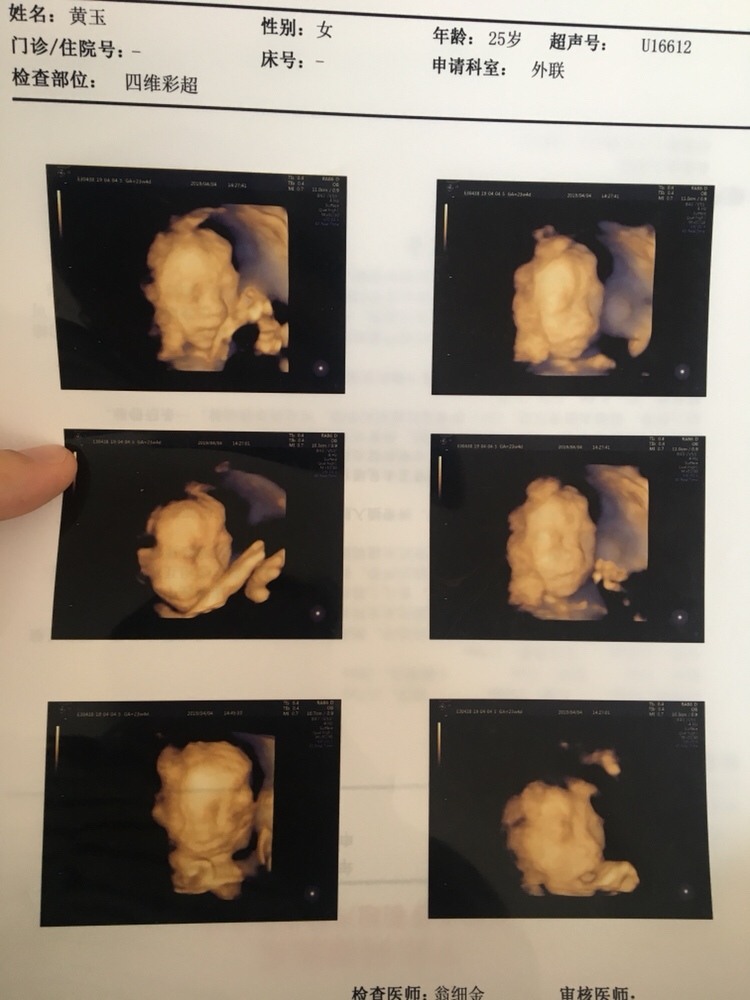

宝宝4个月18天

乔治